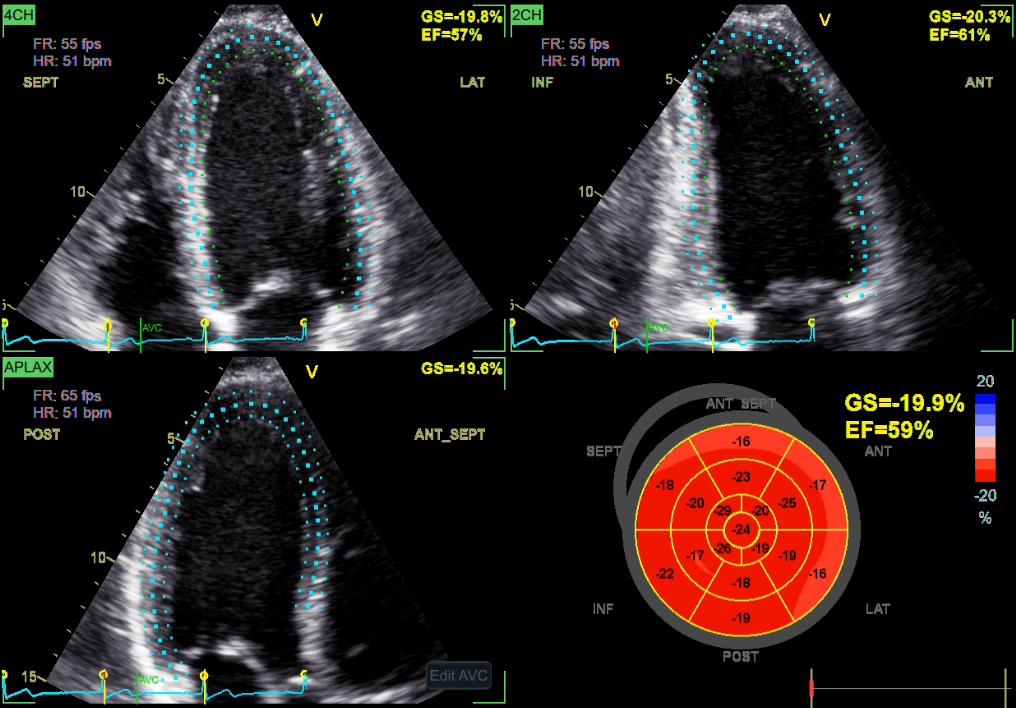

«Mi experiencia con esta tecnología ha sido muy buena, los procesos automatizados permiten un análisis cardíaco avanzado rápido y un mejor flujo de trabajo»

Dr. Edgar Quispe

Cardioncólogo